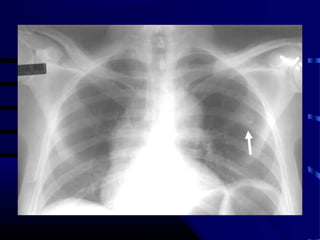

Question

• Patient is a 65 year old smoker with

following CXR and CT scan of chest:

• What test do we order next?

• A. CT-guided lung biopsy.

• B. Video Assisted Thoracic Surgical open

lung biopsy with possible lobectomy.

• C. PET scan.

• D. PFT’s.

• E. CT scan of head.

Alternative Answer

• Mediastinoscopy or Transbronchial Needle

Aspiration (TBNA)

– would also have been an appropriate method of

staging mediastinum.